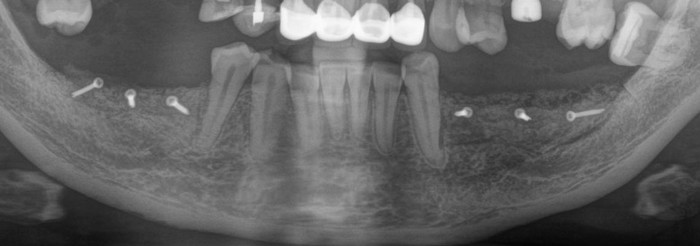

Контрольный рентгеновский снимок:

Вот так было: